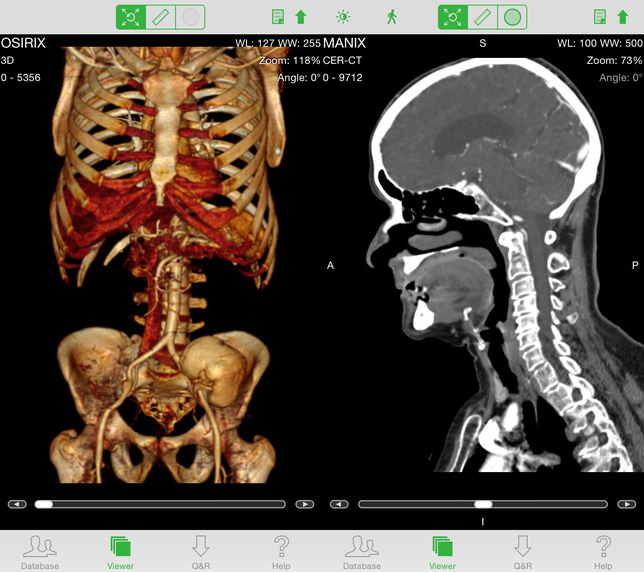

OsiriX HD

2010年,OsiriX团队成立了公司Pixmeo,旗下有三款产品。OsiriX是免费与完全开源的DICOM阅读器。OsiriX MD是FDA批准的二级医疗器械设备,也通过欧洲CE( European Directive 93/42/EEC)认证,在数码影像领域有超过10年的研究与发展,完全支持DICOM标准,因此能轻易整合到工作平台中,采用2D,3D等高级处理分析技术,与PACS完全整合,OsiriX MD售价699美元。 OsiriX HD,是iPhone和iPad使用的APP。OsiriX HD是iOS系统软件,支持在iOS移动终端上直接下载与管理系列图像,能展示任何医学影像图,包括超声、CT扫描、MRI、PET等。这款APP能无缝对接任何DICOM兼容软件,包括影像存储与传输系统PACS,医疗工作站等其他获取型模型。通过触屏缩放,平移、旋转、观察和调整图像对比度,是互动视觉化软件,能展示分析医疗图像。